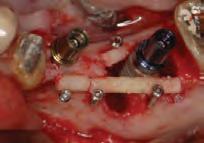

After the patient provided signed informed consent, the tooth was anesthetized and isolated with a rubber dam. Caries was removed and access to the pulp chamber was made using a round diamond bur. The pulpal floor was examined using dental operating microscope (Global Dental Microscopes, Global Surgical Corporation, USA). The DG-16 endodontic explorer (American Eagle, CA, USA) was used to determine the bifurcation level of the root. Ultrasonic tips (Pro Ultra Endo Tips Dentsply Maillefer, Ballaigues, Switzerland) were then used to remove cervical dentin that obstructing the path to lingual canal in mandibular canine. The internal anatomy confirmed the presence of 2 root canal orifices, one located buccally and the other lingually. The working lengths of each canal were estimated by means of electronic apex locator (Root ZX, Morita, Tokyo, Japan), then confirmed by a radiograph.

The canals were initially instrumented with a size #15 K-file, and coronal flaring was carried out using Gates Glidden burs (numbers 3 and 2; Dentsply Maillefer, Ballaigues, Switzerland). Biomechanical preparation was completed by using rotary nickel-titanium files ProTaper Gold (Dentsply Maillefer, Ballaigues, Switzerland) up to apical file size # 30. Copious irrigation with 3% sodium hypochlorite (NaOCl) with ultrasonic Endo Activator (Dentsply Maillefer, Ballaigues, Switzerland) was applied for 30 second followed by 17% Ethylenediaminetetraacetic acid (EDTA) for 1 minute with safe 2-side vents irrigation tips IrriFlex (Produits Dentaires, Swizterland), to remove the inorganic tissues, and this was performed during the instrumentation phase. Sterile paper points were used to dry the root canals. Master cone radiograph was taken, and the two canals were obturated with Tubli-seal (Kerr UK, Peterborough, U.K.) and laterally condensed using gutta-percha points. Final radiographs were taken to ensure proper obturation. A sterile cotton pellet was then placed in the pulp chamber, and IRM cement (Dentsply De Trey GmbH, Konstanz, Germany) was applied to seal the access cavity as a temporary filling to prevent coronal leakage. The patient was referred for final restoration (Fig. 2)